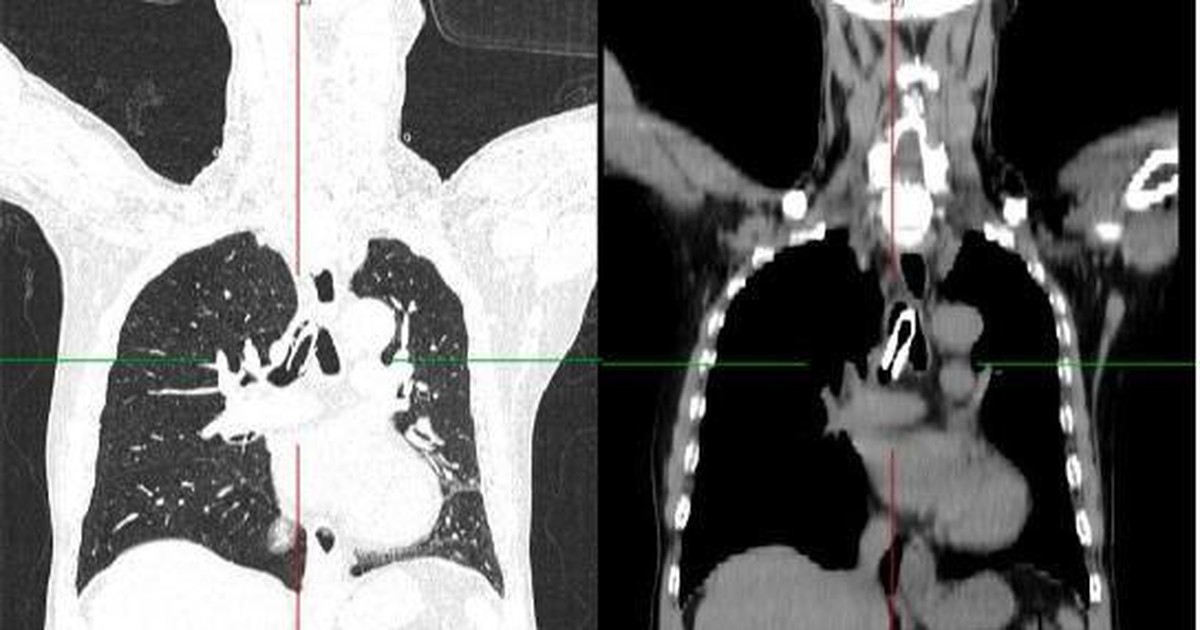

Hai tuần gần đây, số bệnh nhân nhập viện vì cúm A tiếp tục tăng, trong đó có một số trường hợp tổn thương phổi nặng, phải can thiệp ECMO.